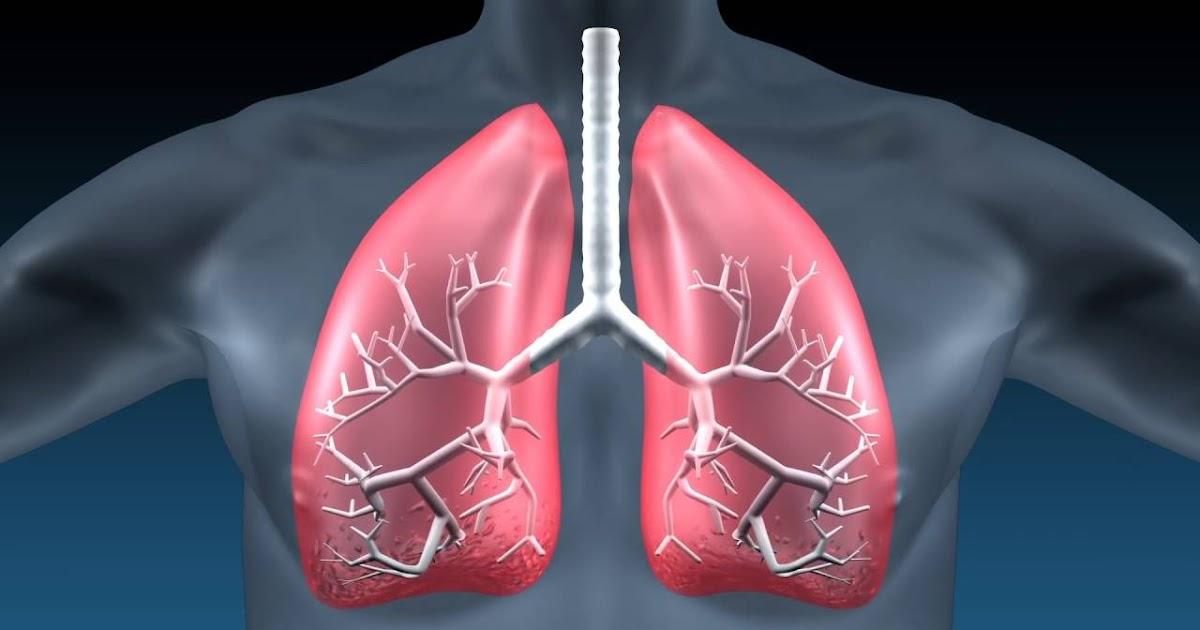

The idiopathic pulmonary fibrosis market has seen significant growth in recent years owing to the rising prevalence of the disease globally. Idiopathic pulmonary fibrosis is a lung disease that causes progressive scaring or thickening of lung tissue which makes breathing difficult. The exact cause of idiopathic pulmonary fibrosis is unknown in majority of cases but it mostly occurs in older adults. Some of the symptoms of IPF include shortness of breath, dry cough, fatigue and finger clubbing. If left untreated, the average life expectancy of an IPF patient is around 2-5 years. Currently, there is no cure for IPF but medications and oxygen therapy can help reduce symptoms and improve quality of life.